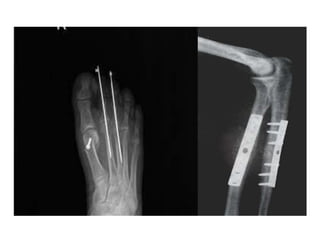

INTERNAL FIXATION

-Bone fragments may be fixed with screws, a

metal plate held by screws, a long intramedullary

rod or nail (with or without locking screws),

circumferential bands or a combination of these

methods.

-Properly applied, internal fixation holds a

fracture securely so that movement can begin at

once; with early movement the ‘fracture disease’

(stiffness and edema) is abolished.

INTERNAL FIXATION -Bone fragmentsmay be fixed with screws, a metal plate held by screws, a long intramedullary rod or nail (with or without locking screws), circumferential bands or a combination of these methods. -Properly applied, internal fixation holds a fracture securely so that movement can begin at once; with early movement the ‘fracture disease’ (stiffness and edema) is abolished.